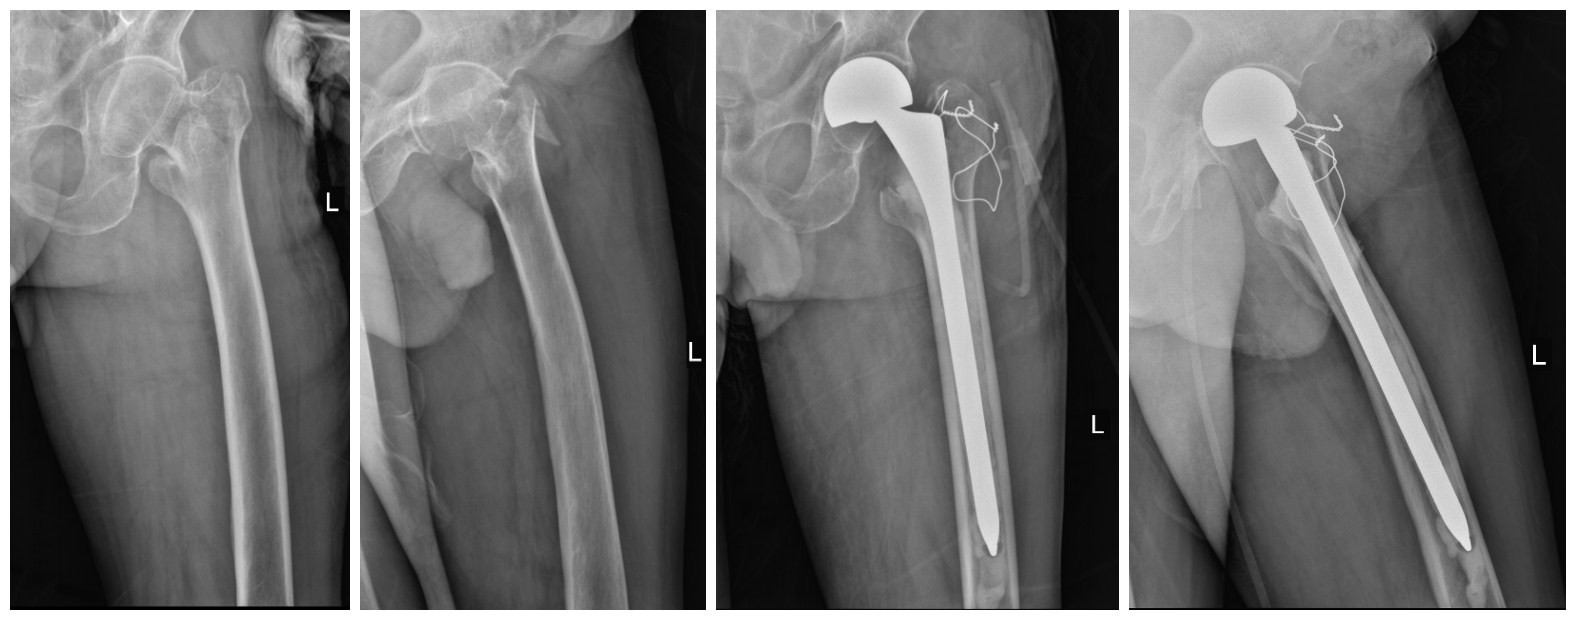

附部分骨折患者术前、术后照片

半髋置换